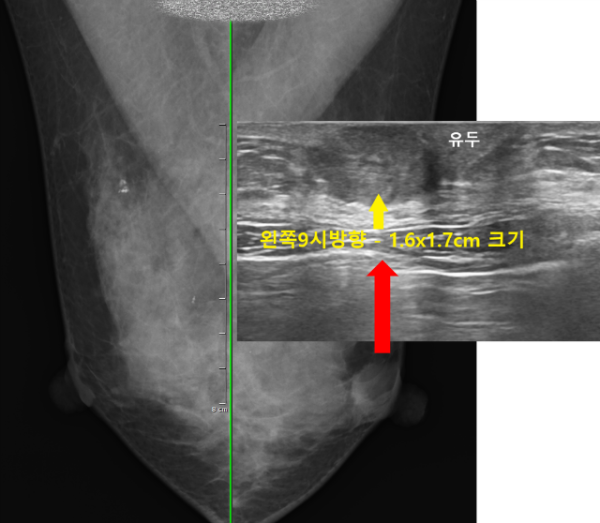

먼저 유방촬영을 시행하였습니다.

유방촬영상 왼쪽 유두하부에 오른쪽과 다른 종괴 소견이 관찰되었습니다.

이어서 유방초음파검사를 진행하였습니다.

왼쪽 유방의 9시방향, 바로 유두아래쪽에 가로x세로의 길이가 약 1.6x1.7cm 크기의 타원형 모양의 결절이 관찰되었습니다.